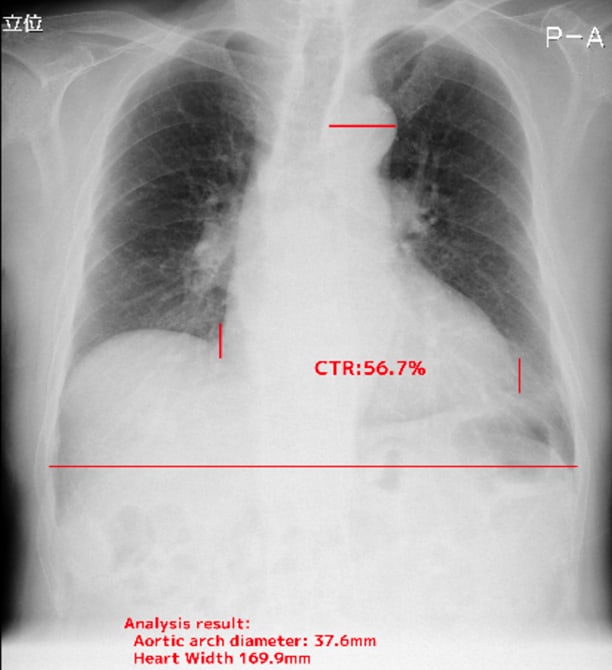

- 心胸郭比

- 大動脈弓の径

自動計測機能